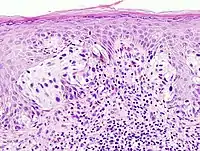

Malignant melanoma of the skin. This is a section of tissue, stained with hematoxylin & eosin, and viewed on a microscope slide